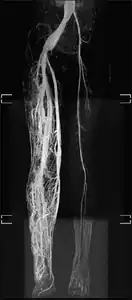

MRI: This is a high-resolution scan that is used to identify the extent of the hypertrophy or overgrowth of the tissues. This can also be used to identify other complications that may arise a result of hypertrophy.[23]

Angiogram: an angiogram can also be ordered to get a detailed look at the blood vessels in the affected or overgrown limb. In this test a physician injects a dye into the blood vessels that will help see how the blood vessels are malformed.[23]

MRI-dilated turtuous blood vessels

Angiogram